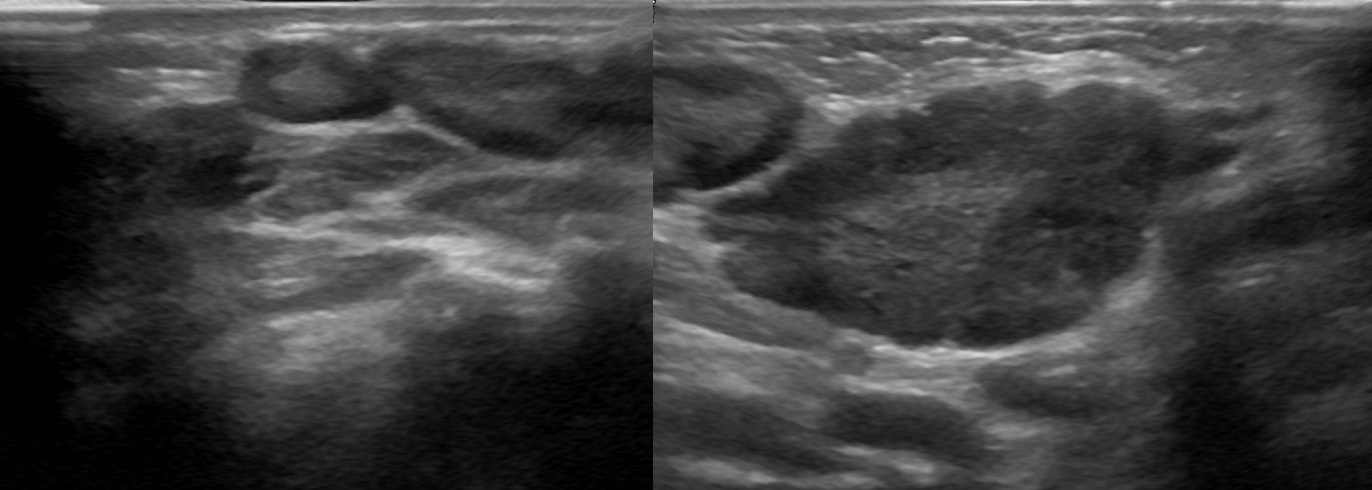

Мезентериальные лимфатические узлы: УЗИ и диагностика

Раздел: Лаборатория идей